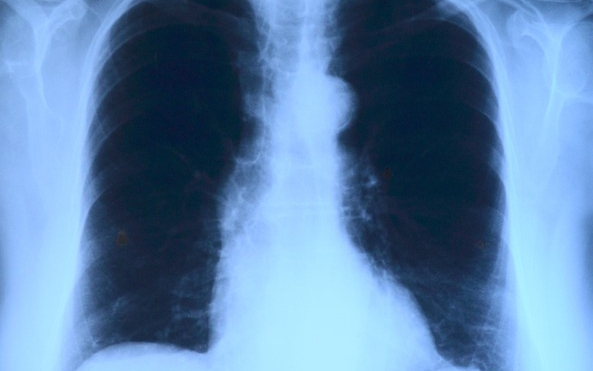

Az országban elsőként a Debreceni Egyetem Klinikai Központjában végeztek tüdőverőér-tágítást - közölte a felsőoktatási intézmény sajtóirodája kedden az MTI-vel.

A nemzetközi orvoscsoport múlt hét szombaton két betegnél hajtotta végre a beavatkozást, amellyel a tüdőerek magas vérnyomását csökkentették. Mindkét páciens krónikus thromboembóliás pulmonális hipetróniában szenvedett, amely súlyos nehézlégzést, kisebb fizikai terhelhetőséget és akár eszméletvesztést is okozhat. Az első hazai ballonos pullmonális értágítást (BPA) Irene Lang professzor, a bécsi Allgemeines Krankenhaus (AKH) kórház II. Belgyógyászat-Kardiológiai osztályának vezetője és tanítványa, Christian Gerges végezte a debreceni kardiológiai és szívsebészeti klinika intervenciós kardiológusainak közreműködésével - olvasható az egyetem közleményében.

A nagy szakértelmet és türelmet igénylő, komplex katéteres eljárást egy 59 éves férfinál és egy 82 éves nőnél végezték el. A 2-3 órás beavatkozás során a tüdő véráramlását akadályozó vérrögöket ballonnal kitágították, így az áramlási akadály mérséklődött, a tüdőerekben pedig csökkent a nyomás, ezzel együtt a szív terhelése is.